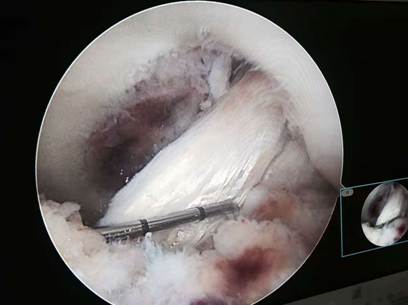

我科为国家中医药管理局“十二五”重点专科建设单位。拥有进口关节镜全套设备、髋膝肩肘人工关节置换全套体系、TDP治疗仪、电脑中频透热治疗仪、多功能微波治疗仪、中药煎药机、下肢功能锻炼机等诊疗设备。根据国内外关节外科发展方向,充分应用中医药发展优势,创立中西医结合特色。近年来已开展了髋、膝、肘、肩等关节人工置换术1000余例,每年各种关节置换100多例,各种关节镜微创手术、运动损伤致各种肌腱、韧带损伤修补重建手术200余例及各种关节骨折内固定手术近400余例,数量和质量居市内各大医院前列。本科室主持两项自治区科研课题两项,市科研6项,在国家杂志发表论文60余篇,研究了跌打散、郁金散、跌打郁金膏、驳骨膏、跌打追风酒、损伤外洗合剂等二十余种纯中药制剂,为满足患者术后快速康复需要,进一步开发了中药止痛贴、消肿贴、痛风贴等外用制剂,广泛运用临床。

②运动医学、关节镜等微创技术:如半月板修补、膝关节交叉韧带重建术、腕管综合征松解术、肩袖修补术等;

擅长中西医结合治疗骨科各种疑难疾病:骨质疏松、慢性腰腿痛、运动损伤、各种关节疾病、复杂关节内骨折、运动损伤、儿童骨骼发育异常等疾病。专长:髋、膝、肩等关节置换、翻修术,复杂关节骨折固定术、前后交叉韧带、半月板损伤、肩关节、踝关节等韧带重建微创手术。

擅长各种四肢骨关节疾病及运动创伤的治疗,各种四肢及复杂关节内骨折内固定术,尤其擅长各种人工关节置换术、翻修术及各种微创关节镜手术如膝关节交叉韧带重建、半月板损伤修复等治疗及基础、临床研究工作。

擅长半月板损伤、交叉韧带损伤、膝关节复杂多韧带损伤、肩袖损伤、复发性肩关节脱位、踝、肘、腕关节等各关节运动损伤的中西医治疗和关节镜微创手术技术;骨关节炎等各种骨关节疾病、复杂关节内骨折的诊治;四肢骨折手术治疗 ,人工关节置换术等。